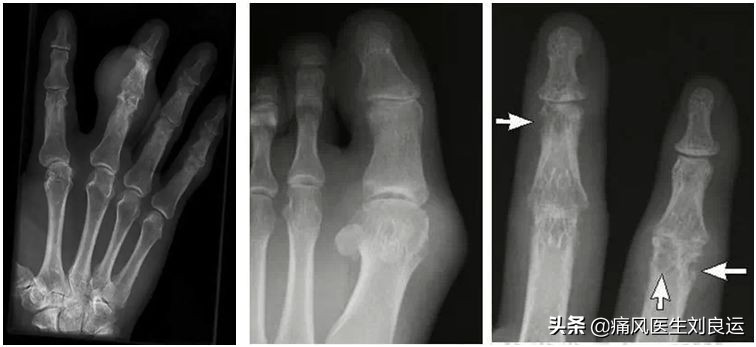

- DR检测:可以发现手或足至少有一处骨侵蚀,一般在疼痛或受累关节周围软组织偏侧性或弥漫性局限性膨大,有时可以见到密度增高、皮肤或皮下脂肪明显有分界及肌间脂肪线模糊、皮下和肌间脂肪密度增高,软组织肿胀多为唯一的X线表现,而且早期为可逆性。

痛风急性发作期的X线表现

通常来说,通过这些相关的检查,不仅能区分其他脚痛与痛风,而且能区分类风湿关节炎、化脓性关节炎、蜂窝组织炎、假性痛风等。